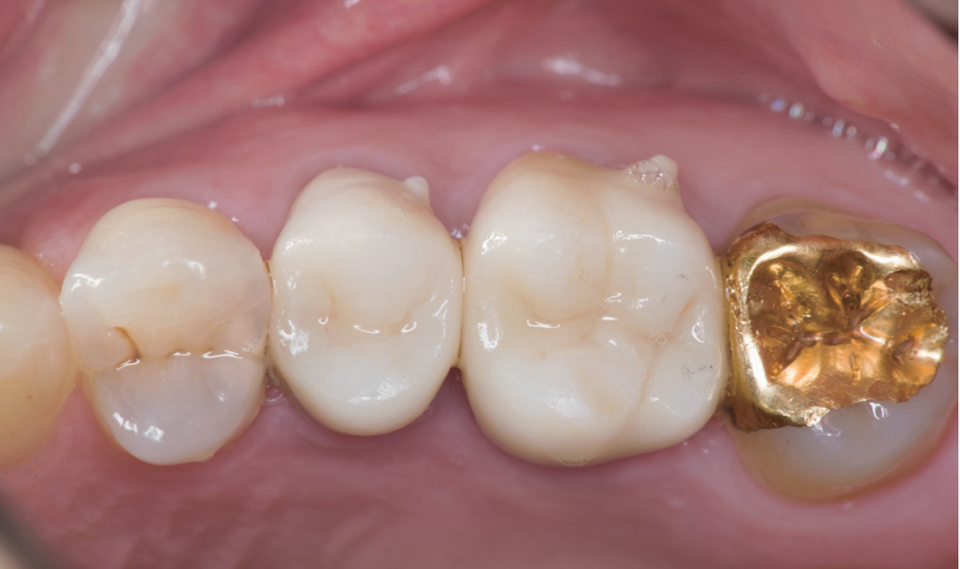

#14~#16 레진 충전

왜 이런 과정을 사진으로 기록할까? 개원한 치과의사는 누구의 간섭도 받지 않고 자신의 양심과 임상능력을 따라 진료한다. 임상 과정을 사진으로 기록하고 정리하는 과정에서 자신의 부족한 점이 드러난다. 최종 치료결과가 좋을 때는 자신감과 직업적인 보람을 얻기도 한다.